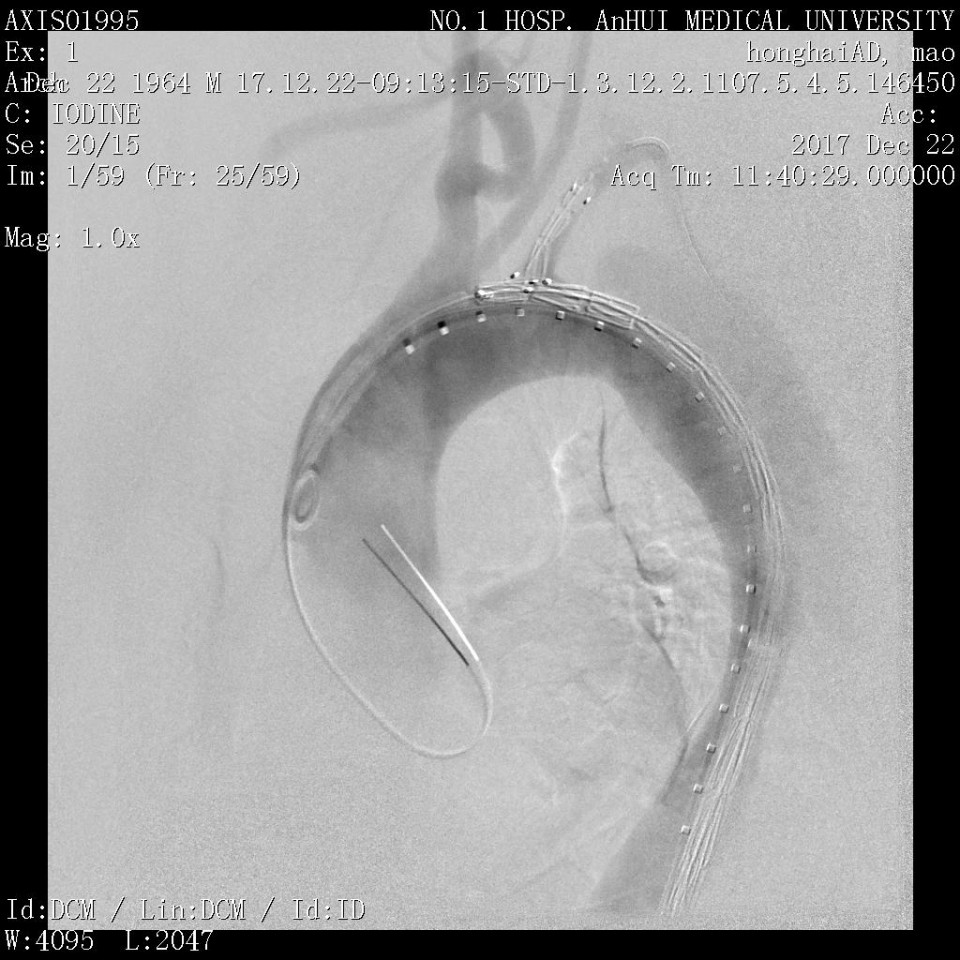

近日,我院血管外科成功应用Castor分支型支架(图1)治疗胸主动脉夹层一例,该病例为我省的首例植入。患者男性,53岁,因“突发胸痛2天”入院,既往有高血压病史。经CTA检查诊断为胸主动脉夹层,破口距离左锁骨下动脉(LSA)36mm,假腔逆撕至左锁LSA(图2、3)。既往一般选用直管型支架,需要部分或全部封闭LSA,但可能增加脑梗和截瘫风险。考虑到患者年龄较轻又是体力劳动者,经科室讨论决定使用Castor一体式分支型覆膜支架,一方面通过增加健康锚定区 (LCCA-LSA距离+LSA直径),进一步降低支架对于血管壁的刺激,从而降低夹层逆撕的风险;另一方面重建LSA保留功能,且不影响LCCA血流。 整个手术过程顺利,最后造影:Castor分支型支架定位精准,无移位;支架近端三重小波段密封性能良好,无内漏,破口被完全封堵,真腔被打开;LSA及LCCA血流通畅,手术圆满成功。病人术后恢复良好(图4、5、6)。